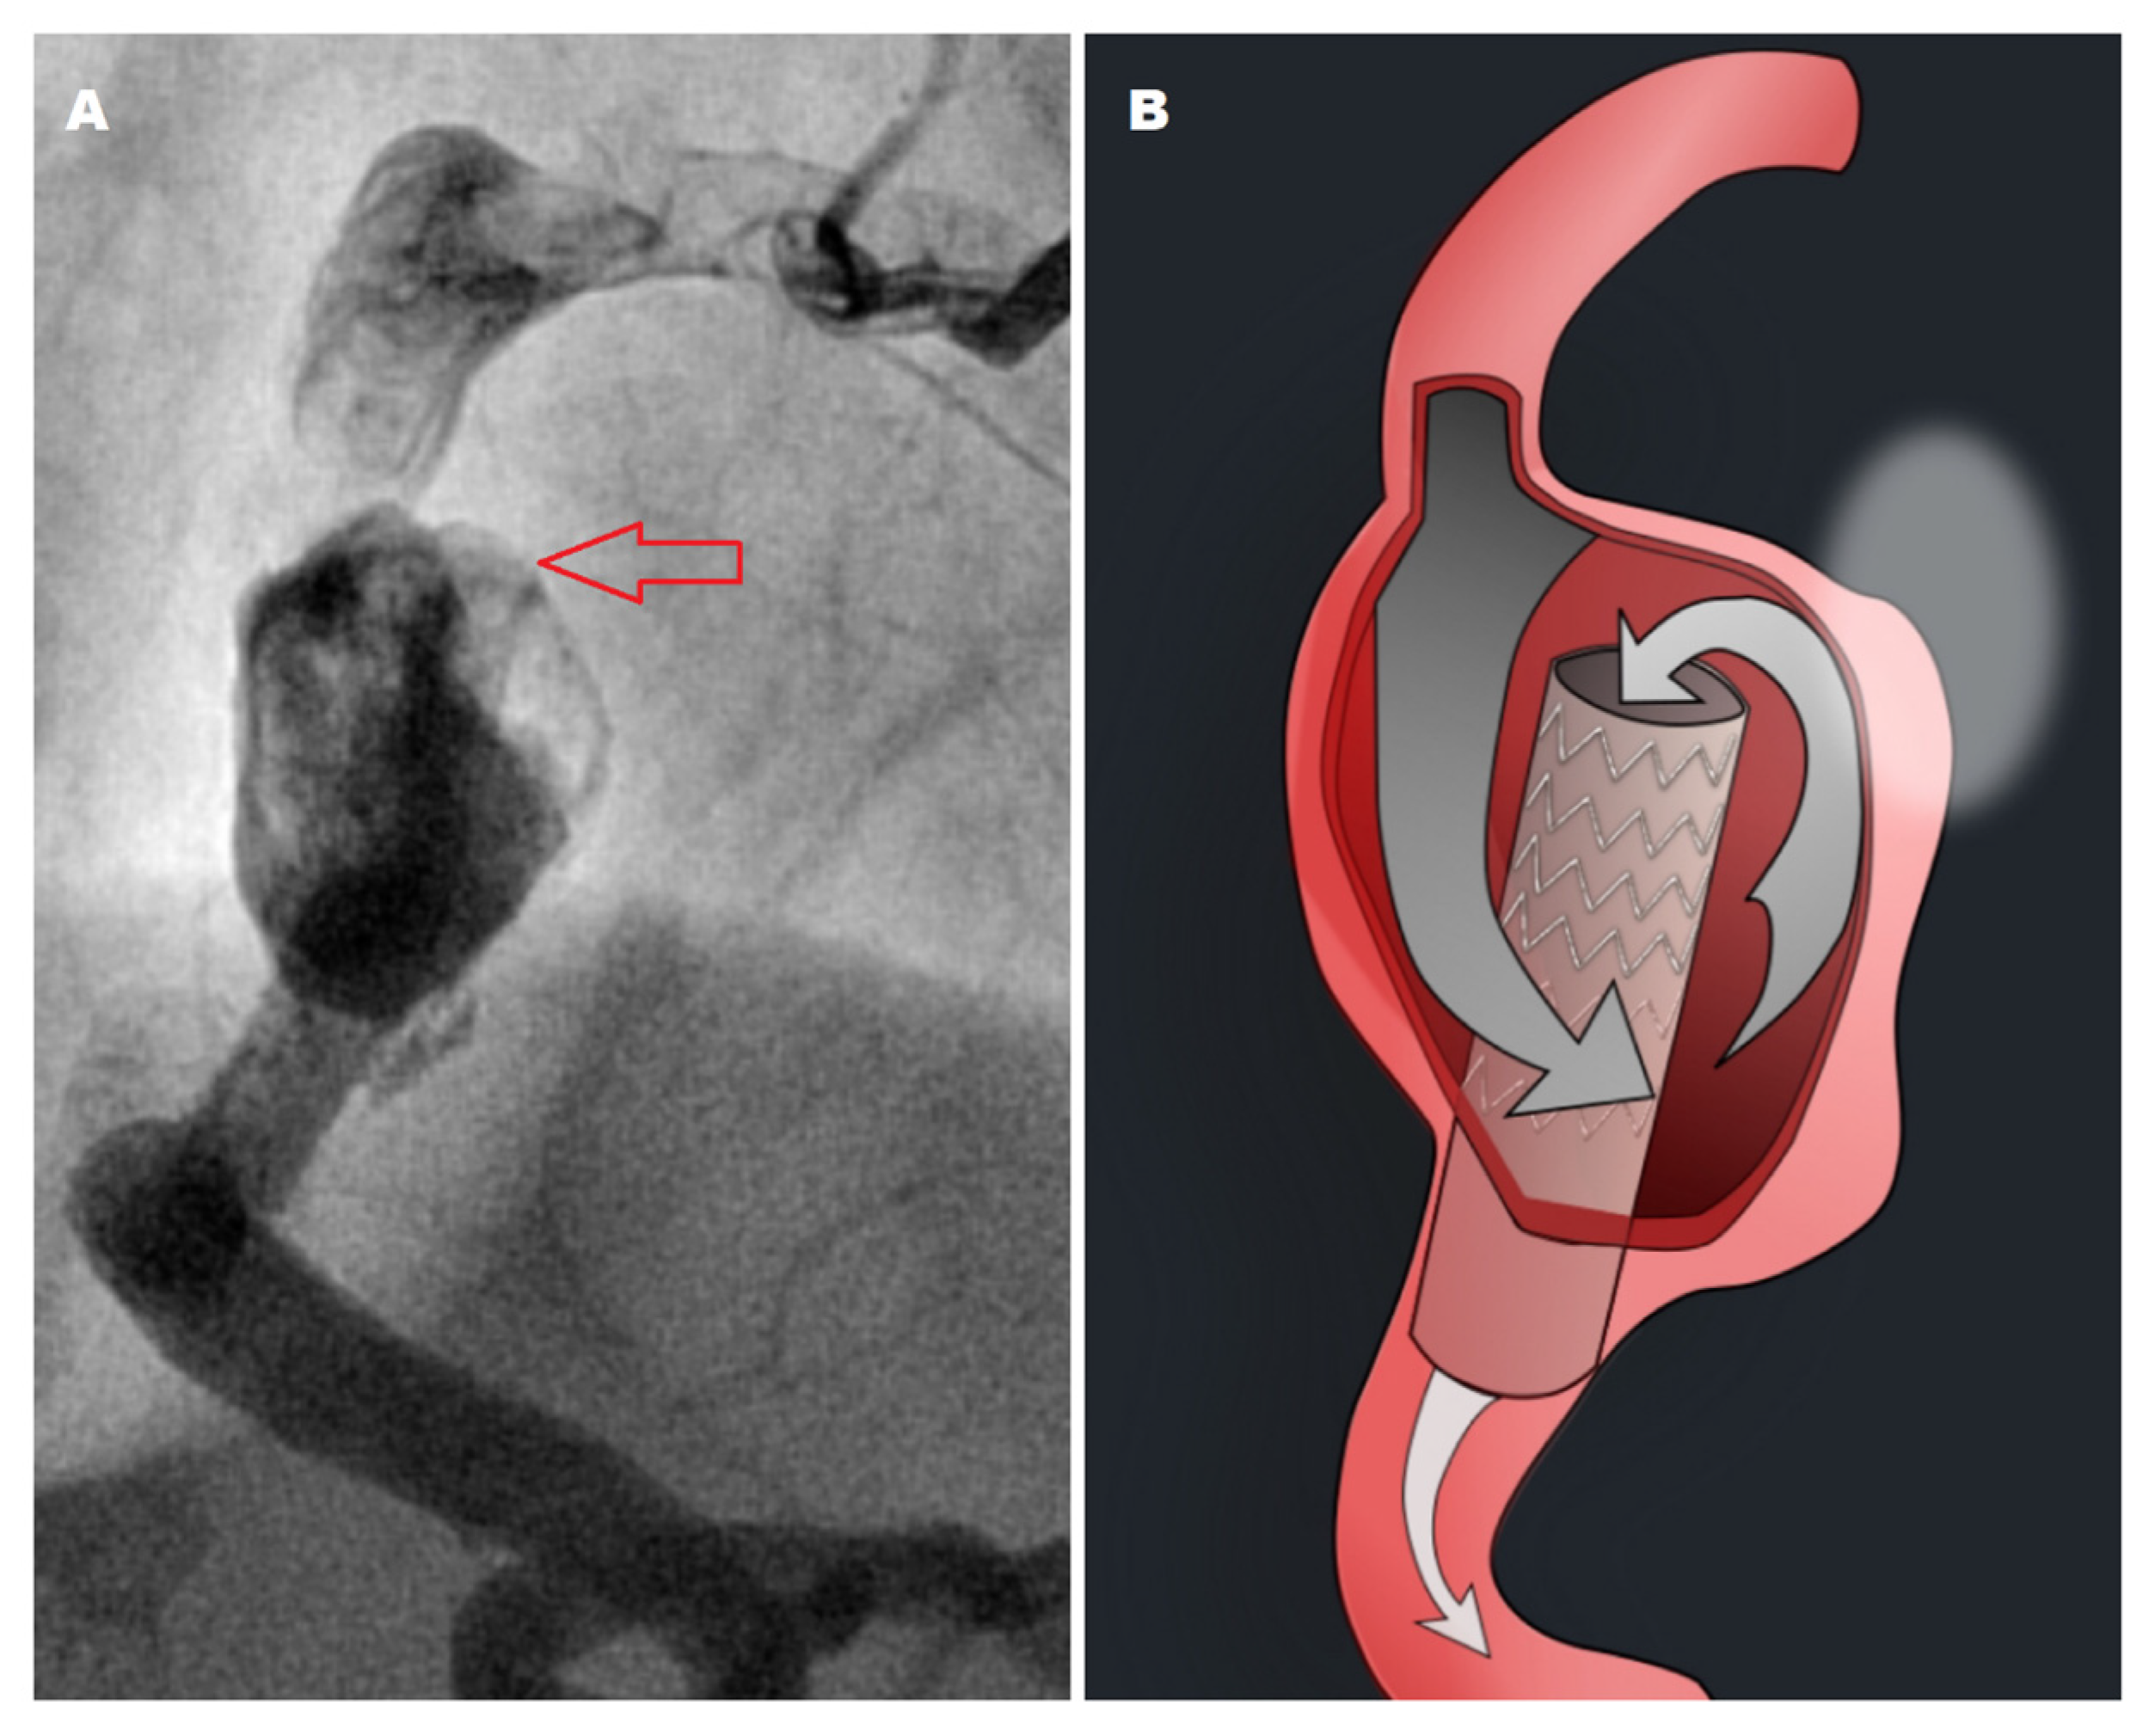

2. Case Presentation